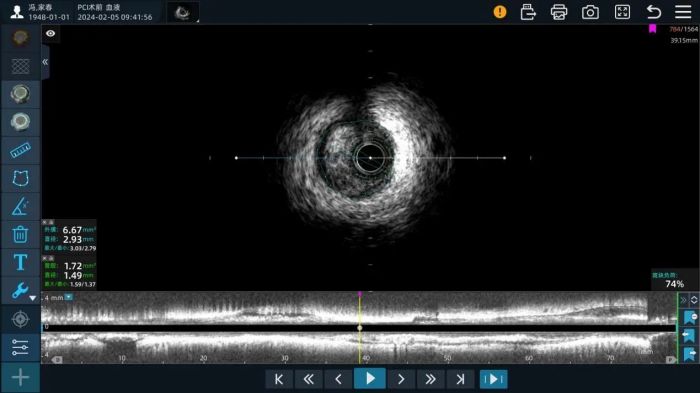

首先处理右冠,在使用2.0*15mm、2.5*15mm预扩球囊对右冠中远段病变充分预处理后,接着送入IVUS-OCT同步陈导管成像(选择单模IVUS成像):IVUS图像清晰,显示右冠中远段第二弯后弥漫性斑块,且以纤维斑块为主,最狭窄处位于中段,MLA:1.72mm2,直径1.49mm,斑块负荷74%。如图(1)结合IVUS检查结果,患者此处病变有行药物球囊扩张成形术的指征,术者团队讨论后最后选择植入2.0*30药物球囊进行治疗。

图(1)